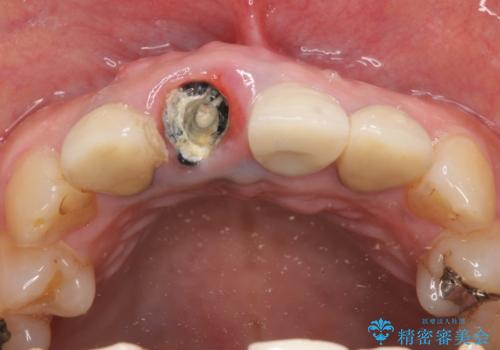

- 右上の前歯が折れてしまったので診て欲しいといらっしゃった方の症例です。

右上1番目の歯は保存不可能だったため抜歯し、ブリッジによる補綴を行いました。